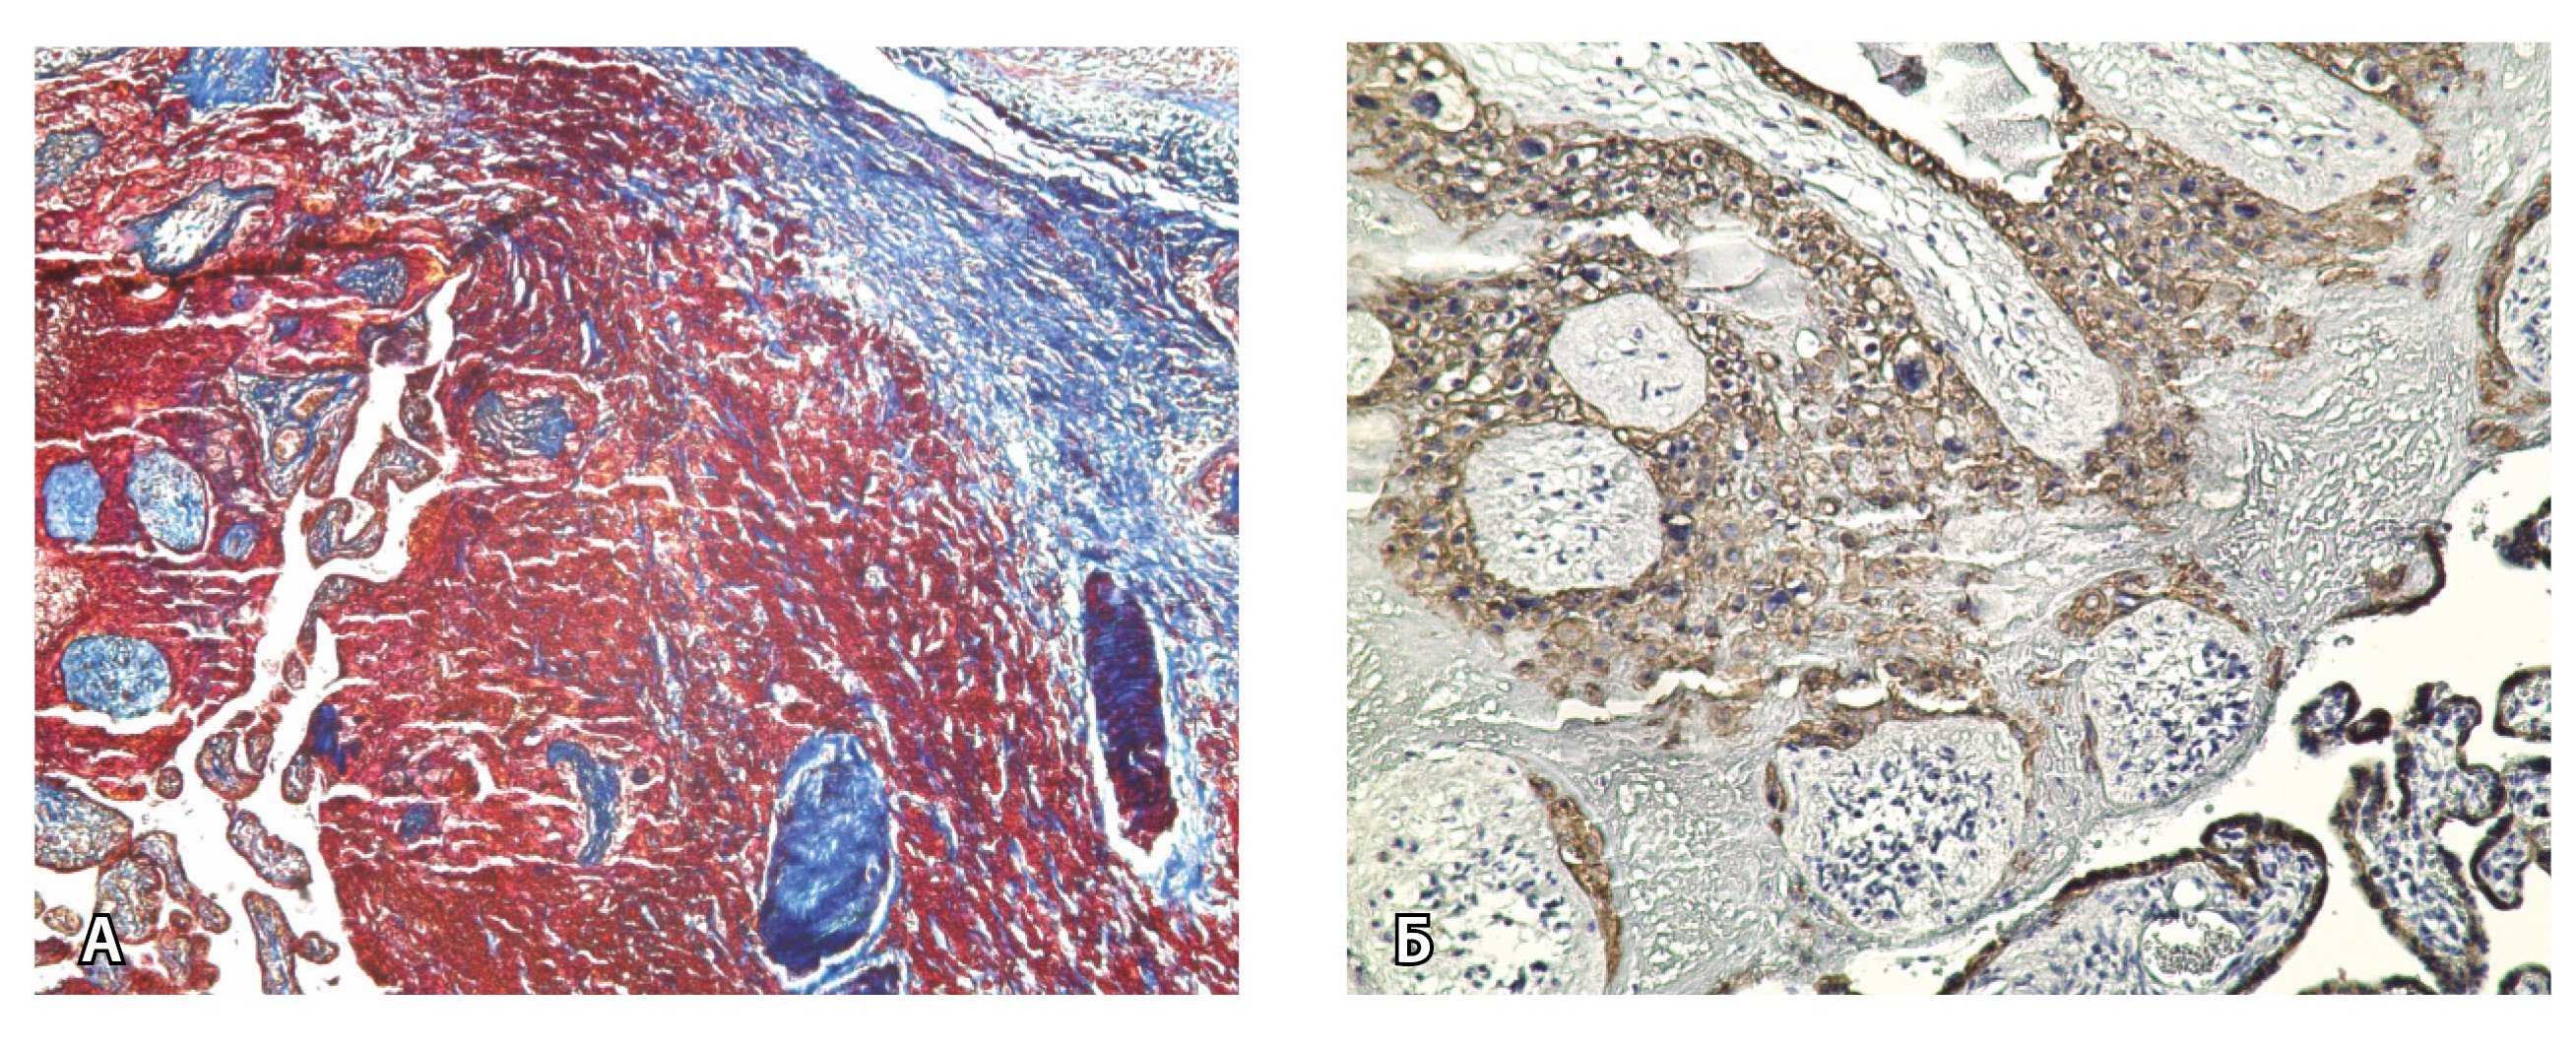

При pl. increta наличие патологических сосудов на изображениях МРТ связано с неполной гестационной перестройкой радиальных артерий, расположенных в срединном слое миометрия. Так, при окраске по Маллори они определяются как сжатые комплексы артерий среднего калибра, с частичным замещением внутренних слоев стенки матки, темно-красными фрагментами плодного фибриноида. На серийных срезах видно, что в этой артерии присутствует достаточное количество инвазивного цитотрофобласта (маркер цитокератин 8), но предыдущий срез подтверждает замещение мышечной оболочки фиброзной тканью как в стенке радиальной артерии, так и в периартериальном пространстве (рис. 8).

Рис. 8. Сосуды 3-го типа при гиперваскуляризации стенки матки при патологической инвазии. Внутриматочная гиперваскуляризация с дефицитом толщины миометрия, наличием рубцовой ткани, недостаточная гестационная перестройка радиальных артерий (аналог pl. increta, PAS 2 по FIGO). А – неполная гестационная перестройка радиальной артерии в составе миометрия (окраска по Маллори; × 50); в верхней части просвета артерии виден слой фибриноида, замещающего эндотелий, такой же фрагмент – в нижней части артерии (стрелка); Б – серийный срез той же радиальной артерии с визуализацией инвазирующего цитотрофобласта (маркер цитокератин 8; × 50); В – серийный срез той же радиальной артерии, при окраске на выявление эластических волокон видна полная дезорганизация эластического каркаса вместо нормальных внутренней и внешней эластических мембран, результат действия инвазирующего цитотрофобласта (окраска по Вейгерту; × 50)

Главным отличием крупных сосудов в составе серозной оболочки является то, что морфологически они находятся в пределах стенки матки. Об этом свидетельствует наличие в операционном материале тонкого поверхностного слоя мезотелия, отделяющего матку от брюшной полости (рис. 11). Его невозможно визуализировать методом МРТ из-за особенностей метода и толщины получаемых срезов.

На микропрепаратах васкуляризация серозной оболочки представлена множеством крупных сосудов, идущих в разных направлениях и анастомозирующих друг с другом. Возможно, имеются артериовенозные соустья. На серийных срезах также видно, что в стенках артерий трудно различимы два слоя миоцитов (продольный и поперечный). Со стороны адвентиции они окружены толстым «футляром» из грубоволокнистой голубой ткани (при окраске по Маллори). Она проникает в стенку артерий, замещая мышечный слой (рис. 12).